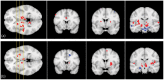

connectivity: dark red means low connectivity, while yellow means high connectivity.